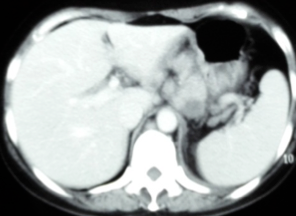

腹部CT:肝胃韧带、肝十二指肠韧带、门腔间隙、胰腺周围、腹主动脉周围多发大小不等的软组织结节影,部分融合成团。

治疗2周期、4周期后肿瘤标志物及CT变化情况如下:

腹膜后淋巴结治疗3月(4周期)